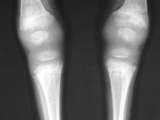

Rickets-both knees

Rickets-both knees